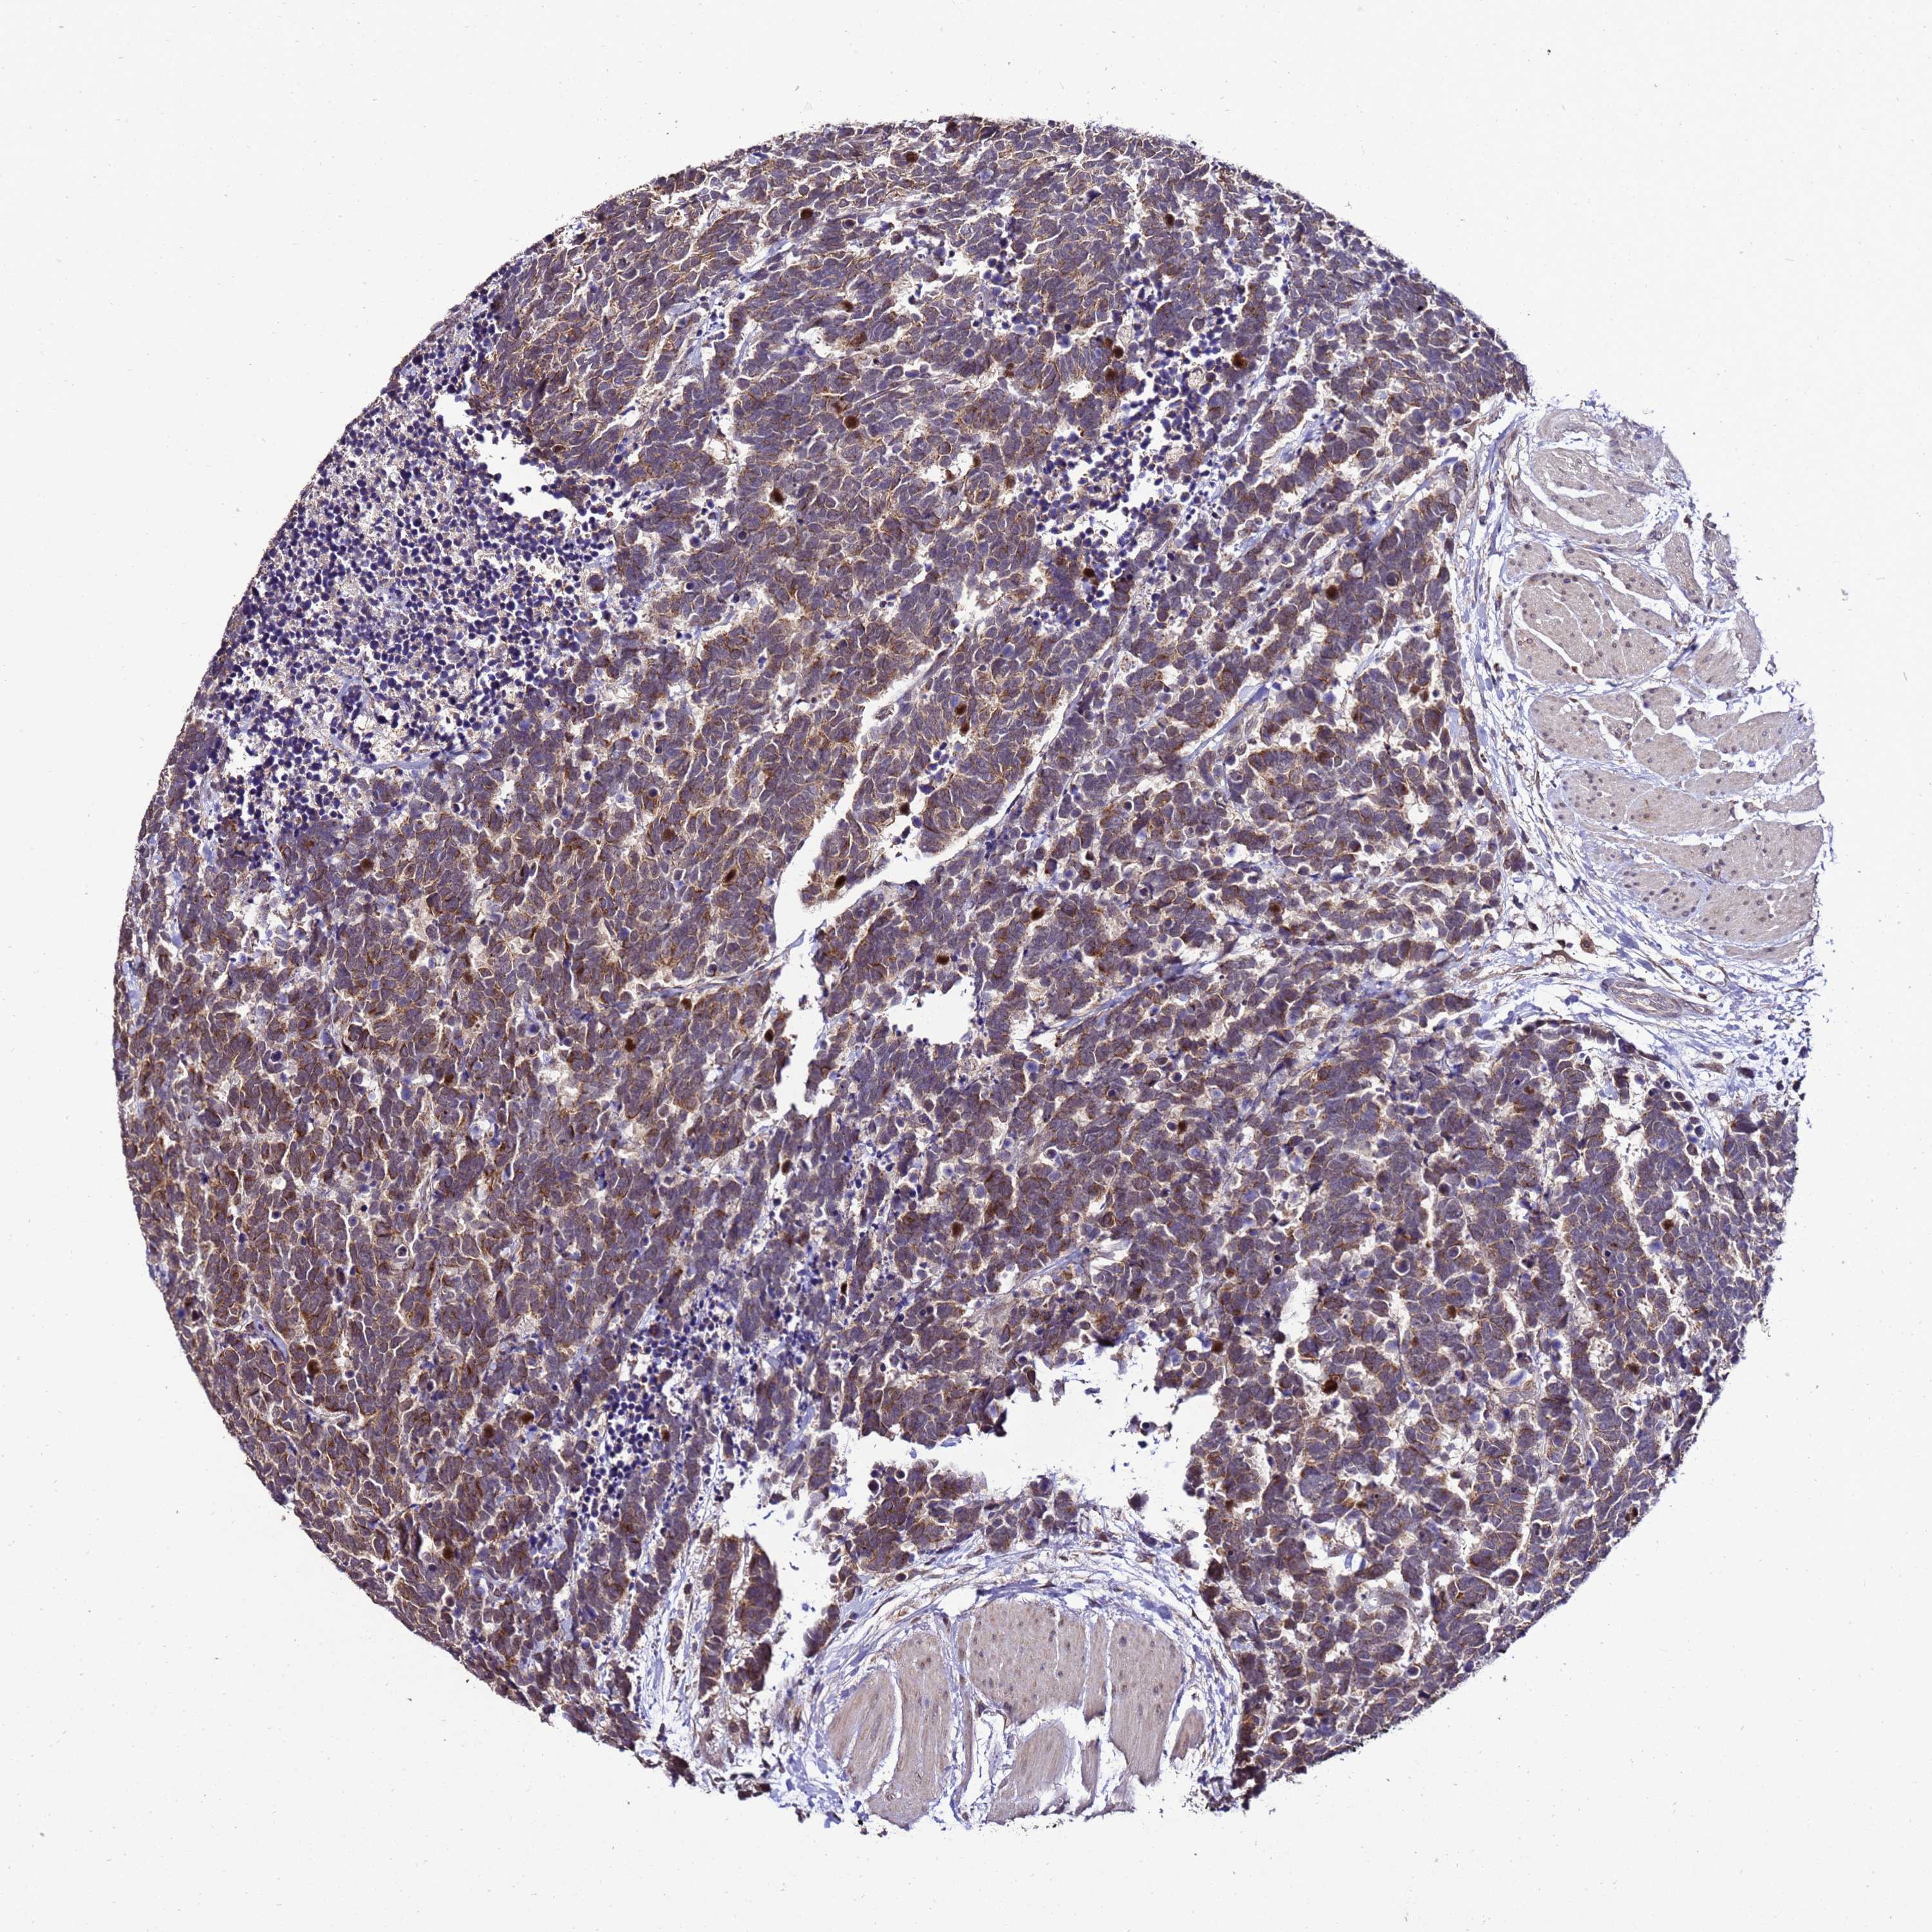

CARCINOID - Protein expressioni

A mouse-over function shows sample information and annotation data. Click on an image to view it in a full screen mode. Samples can be filtered based on level of antibody staining by selecting one or several of the following categories: high, medium, low and not detected. The assay and annotation is described here.

Antibody stainingi

Antibody staining in the annotated cell types in the current human tissue is reported as not detected, low, medium, or high, based on conventional immunohistochemistry profiling in selected tissues. This score is based on the combination of the staining intensity and fraction of stained cells.

Each image is clickable and will lead to virtual microscopy that enables deeper exploration of all samples and also displays staining intensity scores, fraction scores and subcellular localization as well as patient and tissue information for each sample.

Antibody HPA044373

Staining

High

Medium

Low

Not detected

Intensity

Strong

Moderate

Weak

Negative

Quantity

>75%

75%-25%

<25%

None

Location

Nuclear

Cytoplasmic/membranous

Cytoplasmic/membranous,nuclear

Carcinoid, malignant, NOS

Carcinoma, NOS